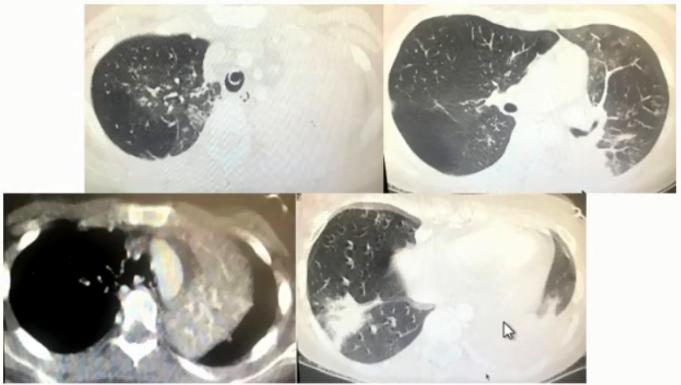

女性,14岁,学生。发热、咳嗽10天入院。

院外治疗经过

• 第1-3天:阿奇霉素治疗3天(口服2天+静脉1天)无效,胸片示左上肺及右下肺斑片影

• 第4-5天:头孢曲松+阿奇霉素+小剂量激素2天无效,肺CT示左上肺大片实变及右下肺斑片影

• 第6-7天:头孢曲松+阿奇霉素+甲泼尼龙40mg bid 2天仍无好转,出现呼吸困难,CT示肺内病变进一步增多,血常规7.8×109/L、N 82.9%,CRP 43.16 mg/L,动脉血气分析PH7.42 PaO246mg Hg。

• 第8-9天:美罗培南+利奈唑胺+甲泼尼龙 80mg/d,体温无下降,呼吸困难加重,吸氧8-10L/min,指脉氧80%左右,G试验154.7,加用伏立康唑,行气管插管机械通气,病情仍无改善转来我院。

院外病原学检查结果

• 痰涂片:偶见G+球菌 呈双排列

• 痰培养:少量假丝酵母菌

• CMV IgG 0.8AU/ml(<6),IgM 0.32(<0.85)

• 甲流及乙流抗原阴性

• 呼吸道病原九项IgM(包括嗜肺军团菌、肺炎支原体、肺炎衣原体等)均阴性

图6 患者在院外胸部影像学变化。左上肺小块实变,逐渐累积至右下肺,而且左上肺实变扩大和膨胀不全。

图7 患者入院当日病情小结

图8 患者入院当日胸部CT。左上肺大面积实变,右上肺斑片影,出现胸腔积液